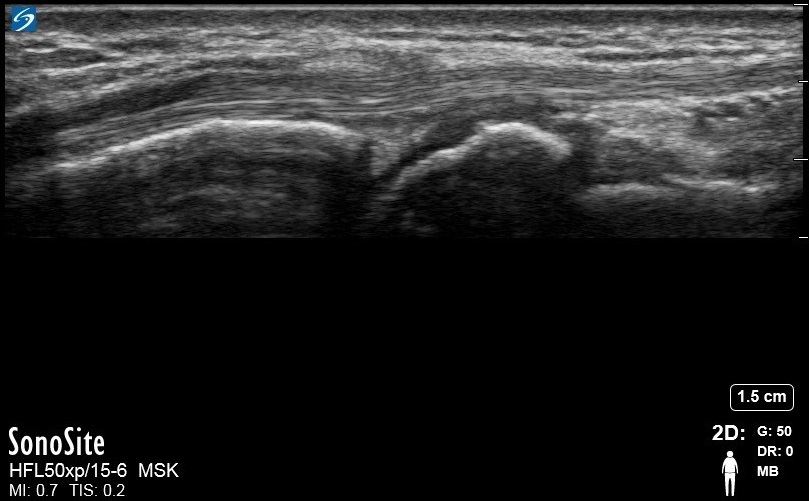

Wrist Extensor Carpi Radialis Brevis and Extensor Carpi Radialis Longus 2 Image